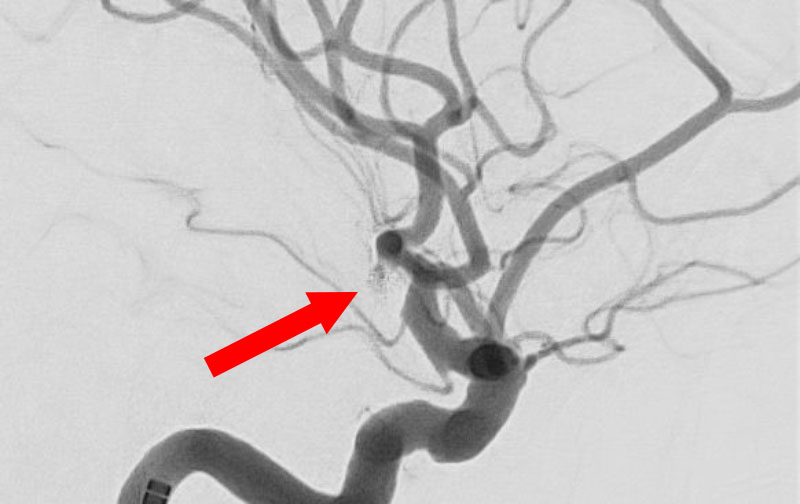

No.1595 手術前

左内頚動脈脳動脈瘤

60代

大阪府の病院